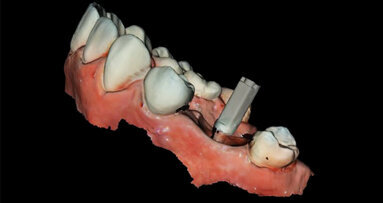

Aplikace MTA s MAP systémem a PD MTA White

Aplikace PD MTA White s MAP systémem

Kondenzace MTA papírovým čepem

Aplikace PD MAP White pomocí MAP systému a kondenzace MTA pluggerem